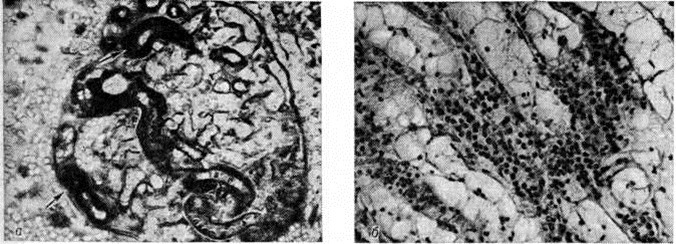

Тромбоз капилляров клубочков как проявление диссеминированного внутрисосудистого свёртывания крови наблюдается чаще при бактериемическом шоке и патологически протекающей беременности. К проявлениям диссеминированного внутрисосудистого свёртывания крови с развитием генерализованного феномена Швартцмана— Санарелли (смотри полный свод знаний: Швартцмана феномен) относят также симметричный кортикальный некроз почек (смотри полный свод знаний: Геморрагический кортикальный некроз почек). Различают тотальную, субтотальную, сегментарную и малую формы некроза. При тотальной форме сохраняются почечные пирамиды; при субтотальной — в корковом веществе встречаются островки непоражённой ткани; при сегментарной — очаги некроза имеют вид инфарктов, окружённых геморрагиями; малые формы удаётся выявить только при микроскопическом исследовании. При затянувшейся острой Почечная недостаточность некротизованное корковое вещество почки истончается. Отравление этиленгликолем влечёт за собой симметричный кортикальный некроз почек, сочетающийся с гликолевым нефрозом, а при патологии беременности — с острой гемоглобинурией, апоплексией и некрозом коркового вещества надпочечников, некрозом передней доли гипофиза. Гистологически отмечается коагуляционный некроз коркового вещества почки. В клубочковых кровеносных капиллярах и артериолах обнаруживают фибриновые тромбы (рисунок 2, а). Зона некроза ограничена демаркационным валом из полиморфно-ядерных лейкоцитов. Аргирофильный каркас разрушен. В дальнейшем некротизированные участки подвергаются организации, фиброзу и кальцинозу.

При гликолевом нефрозе почка увеличена, на разрезе влажная; гистологически определяется баллонная дистрофия эпителия канальцев проксимальных и дистальных отделов нефрона(рисунок 2, б) с кристаллами оксалатов в их просвете и внутри клеток. Электронно-микроскопическое исследование выявляет образование вакуолей в результате резкого расширения цистерн эндоплазматической сети. Нефроциты в состоянии баллонной дистрофии могут длительно не отторгаться, замедляя регенерацию ткани почки.

Острый гемоглобинурийный нефроз развивается при отравлении гемолитическими ядами (уксусной кислотой, мышьяковистым водородом, медным купоросом, аминосоединениями, нитросоединениями и другие). При этом морфологический изменения отражают транспорт гемоглобина по системе нефрона; для макроскопической картины типична черно-бурая радиальная исчерченность почечных пирамид, обусловленная наличием пигментных цилиндров (рисунок 3), дающих положительную реакцию Лепене (смотри полный свод знаний: Лепене способ) с бензидином. При отравлении уксусной кислотой гистологически обнаруживается поражение эпителия канальцев проксимальных отделов нефрона, обусловленное реабсорбцией гемоглобина, который выявляется в виде бензидин-положительных гранул в цитоплазме; при электронно-микроскопическом исследовании обнаруживается резорбция гемоглобина в вакуолях клеток с парциальным некрозом апикальных отделов, «перегруженных» пигментом, процесс сопровождается разрывом канальцев дистальных отделов нефрона с выходом в строму содержимого канальца, воспалительной реакцией вокруг него и последующей его облитерацией. Отравление гемолитическими ядами тиоловой группы (мышьяковистый водород, соединения меди и другие) проявляется острым гемоглобинурийным нефрозом в сочетании с коагуляционным некрозом нефроцитов.